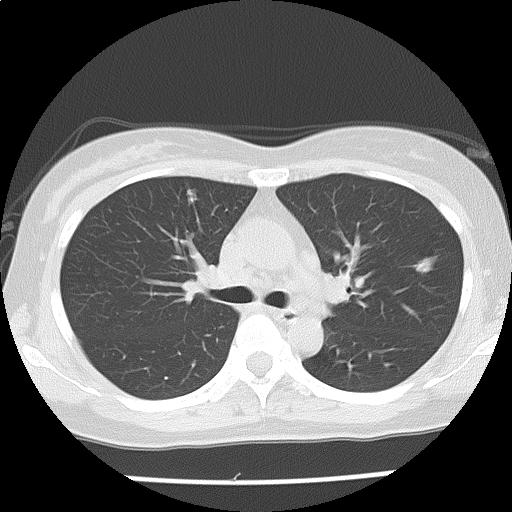

両肺に径数 mm~約9 mm の結節が多発しており(添付画像以外にも認める)、辺縁不整を認める。

多発肺転移の可能性をまず除外する必要があり、原発としては乳癌、膵癌などと考える。

悪性が否定的な場合には、感染症、血管炎、サルコイドーシスなども鑑別に挙げられる。

多発肺結節・縦隔リンパ節腫大:r/o 多発肺転移